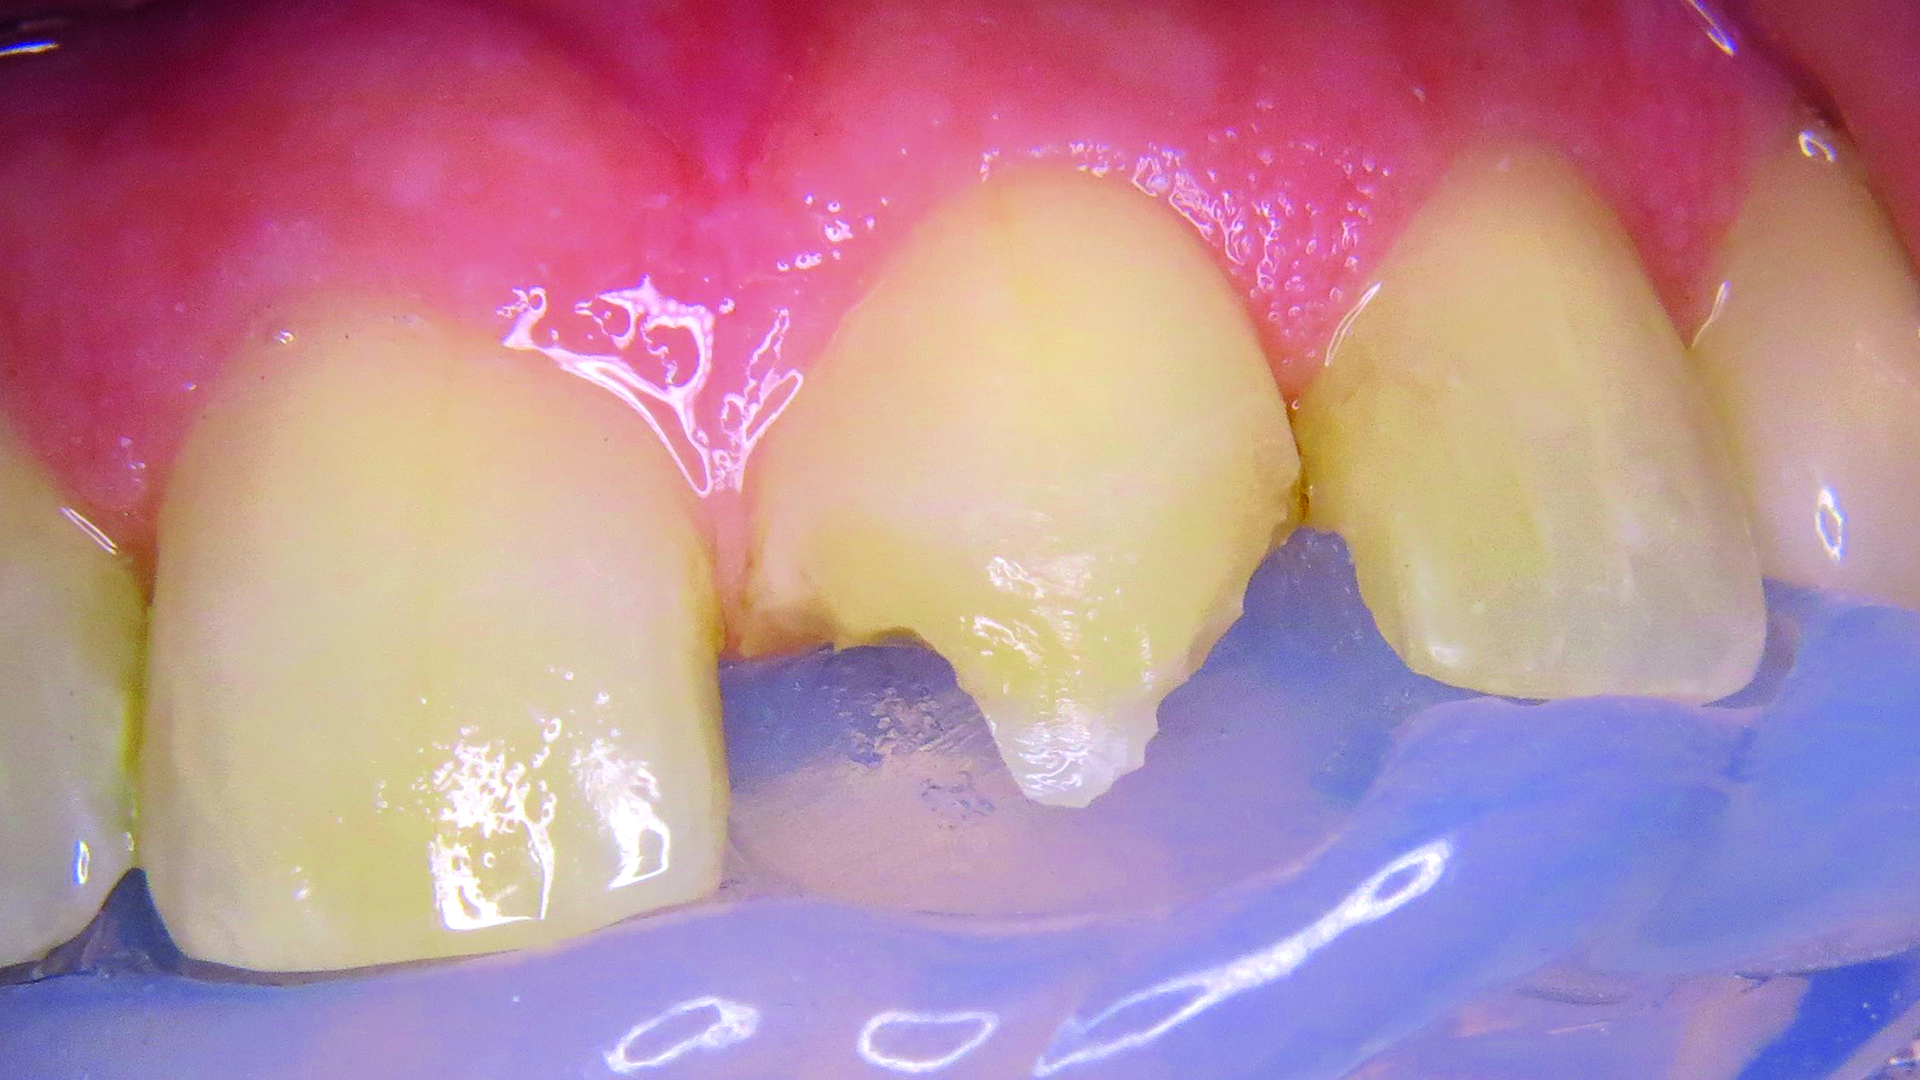

Podano miejscowe znieczulenie nasiękowe preparatem Ultracain D bez adrenaliny (Sanovi-Aventis GmbH, Niemcy), po czym oczyszczono zęby przednie pastą Cleanic bez fluoru (KERR GmbH, Niemcy). Wadliwe wypełnienie usunięto wiertłem z nasypem diamentowym i różyczką, kontrolując dostęp wilgoci (ryc. 4).

Ryc. 4. Stan po usunięciu odbudowy.